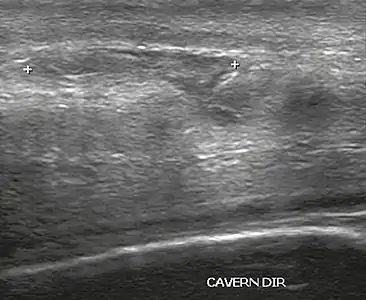

În examinarea cu ultrasunete, o leziune a tunicii albuginea se prezintă ca o întrerupere a (pierderii continuității) liniei ecografice care o reprezintă (Figura 4). Hematoamele mici, moderate sau mari demonstrează gradul de discontinuitate. Hematoamele intracavernoase, uneori fără prezența unei fracturi a tunicii albuginea, pot fi observate atunci când există o leziune a mușchiului neted al trabeculelor care înconjoară spațiile sinusoidale sau plexul venular subtunical. [10]

Figure 4 A: Ultrasound of the penis, right lateral view. Longitudinal section showing rupture of the tunica albuginea with an adjacent 1.92 cm hematoma (between calipers), due to trauma.[10]